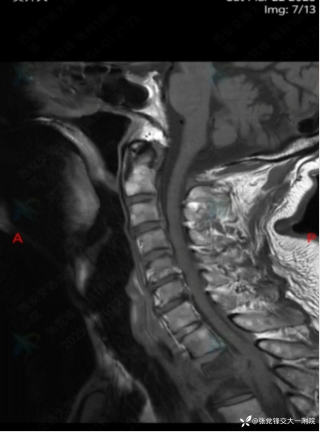

反思 | 赶高铁时一过性晕厥的老年男性

月叔打怪兽急诊科医师

昨天值班遇到的一例晕厥病例,差点漏诊,而最终的解法,始于最简单而质朴的查体。国庆中秋双节的最后一天,8号的早上8点,抢救室床旁晨交班,病人依旧是多而重,交到6床,一个刚入室不久的病人,准备去做CT,夜班医师汇报病史:69岁男性,本次因“头晕伴一过性晕厥1小时”为主诉入抢,1小时前于高铁站因即将赶不上高铁走路快时突发头晕,伴一过性晕厥,约3-4分钟后清醒,清醒后诉今晨未吃早餐,已服用降压药物,仍有头晕头痛、四肢乏力等不适,无胸闷胸痛,无畏寒发热,无咳嗽咳痰,无恶心呕吐,无肢体麻木,无视物模糊等不适,路人拨打120送至我院急诊就诊。既往高血压,长期服用氨氯地平+福辛普利,血压控制一般;糖尿病,长期